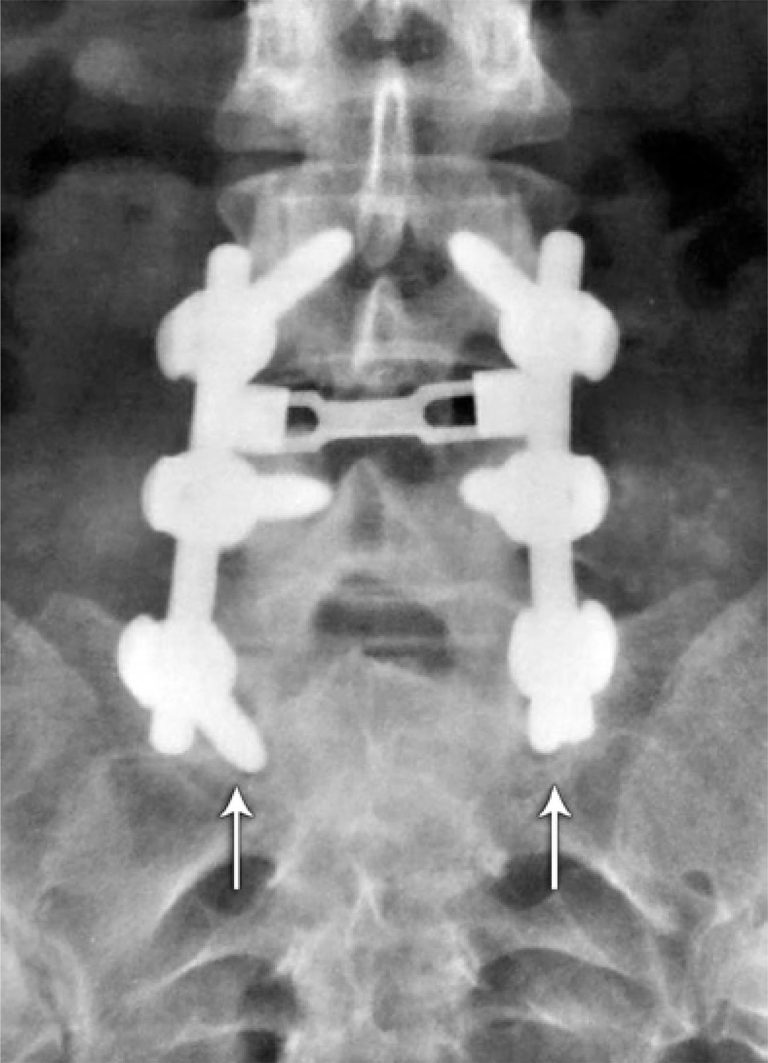

ABSTRACT Objective: To measure the interobserver reproducibility of the radiographic evaluation of lumbar spine instability. Methods: Measurements of the dynamic radiographs of the lumbar spine in lateral view were performed, evaluating the anterior translation and the angulation among the vertebral bodies. The tests were evaluated at workstations of the organization, through the Carestream Health Vue RIS (PACS), version 11.0.12.14 Inc. 2009© system. Results: Agreement in detecting cases of radiographic instability among the observers varied from 88.1 to 94.4%, and the […]